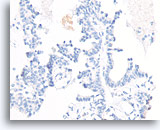

Papilloom, Borst FNA, Celblok.

Immunokleuring met p63 van de coupes van de patiënt in afbeelding 23-25 helpt de myoepitheliale cellen te markeren die door deze papilloom verstrooid zijn.

10X

Papilloom, Borst FNA, Celblok.

Immunokleuring met p63 van de coupes van de patiënt in afbeelding 23-25 helpt de myoepitheliale cellen te markeren die door deze papilloom verstrooid zijn.

10X